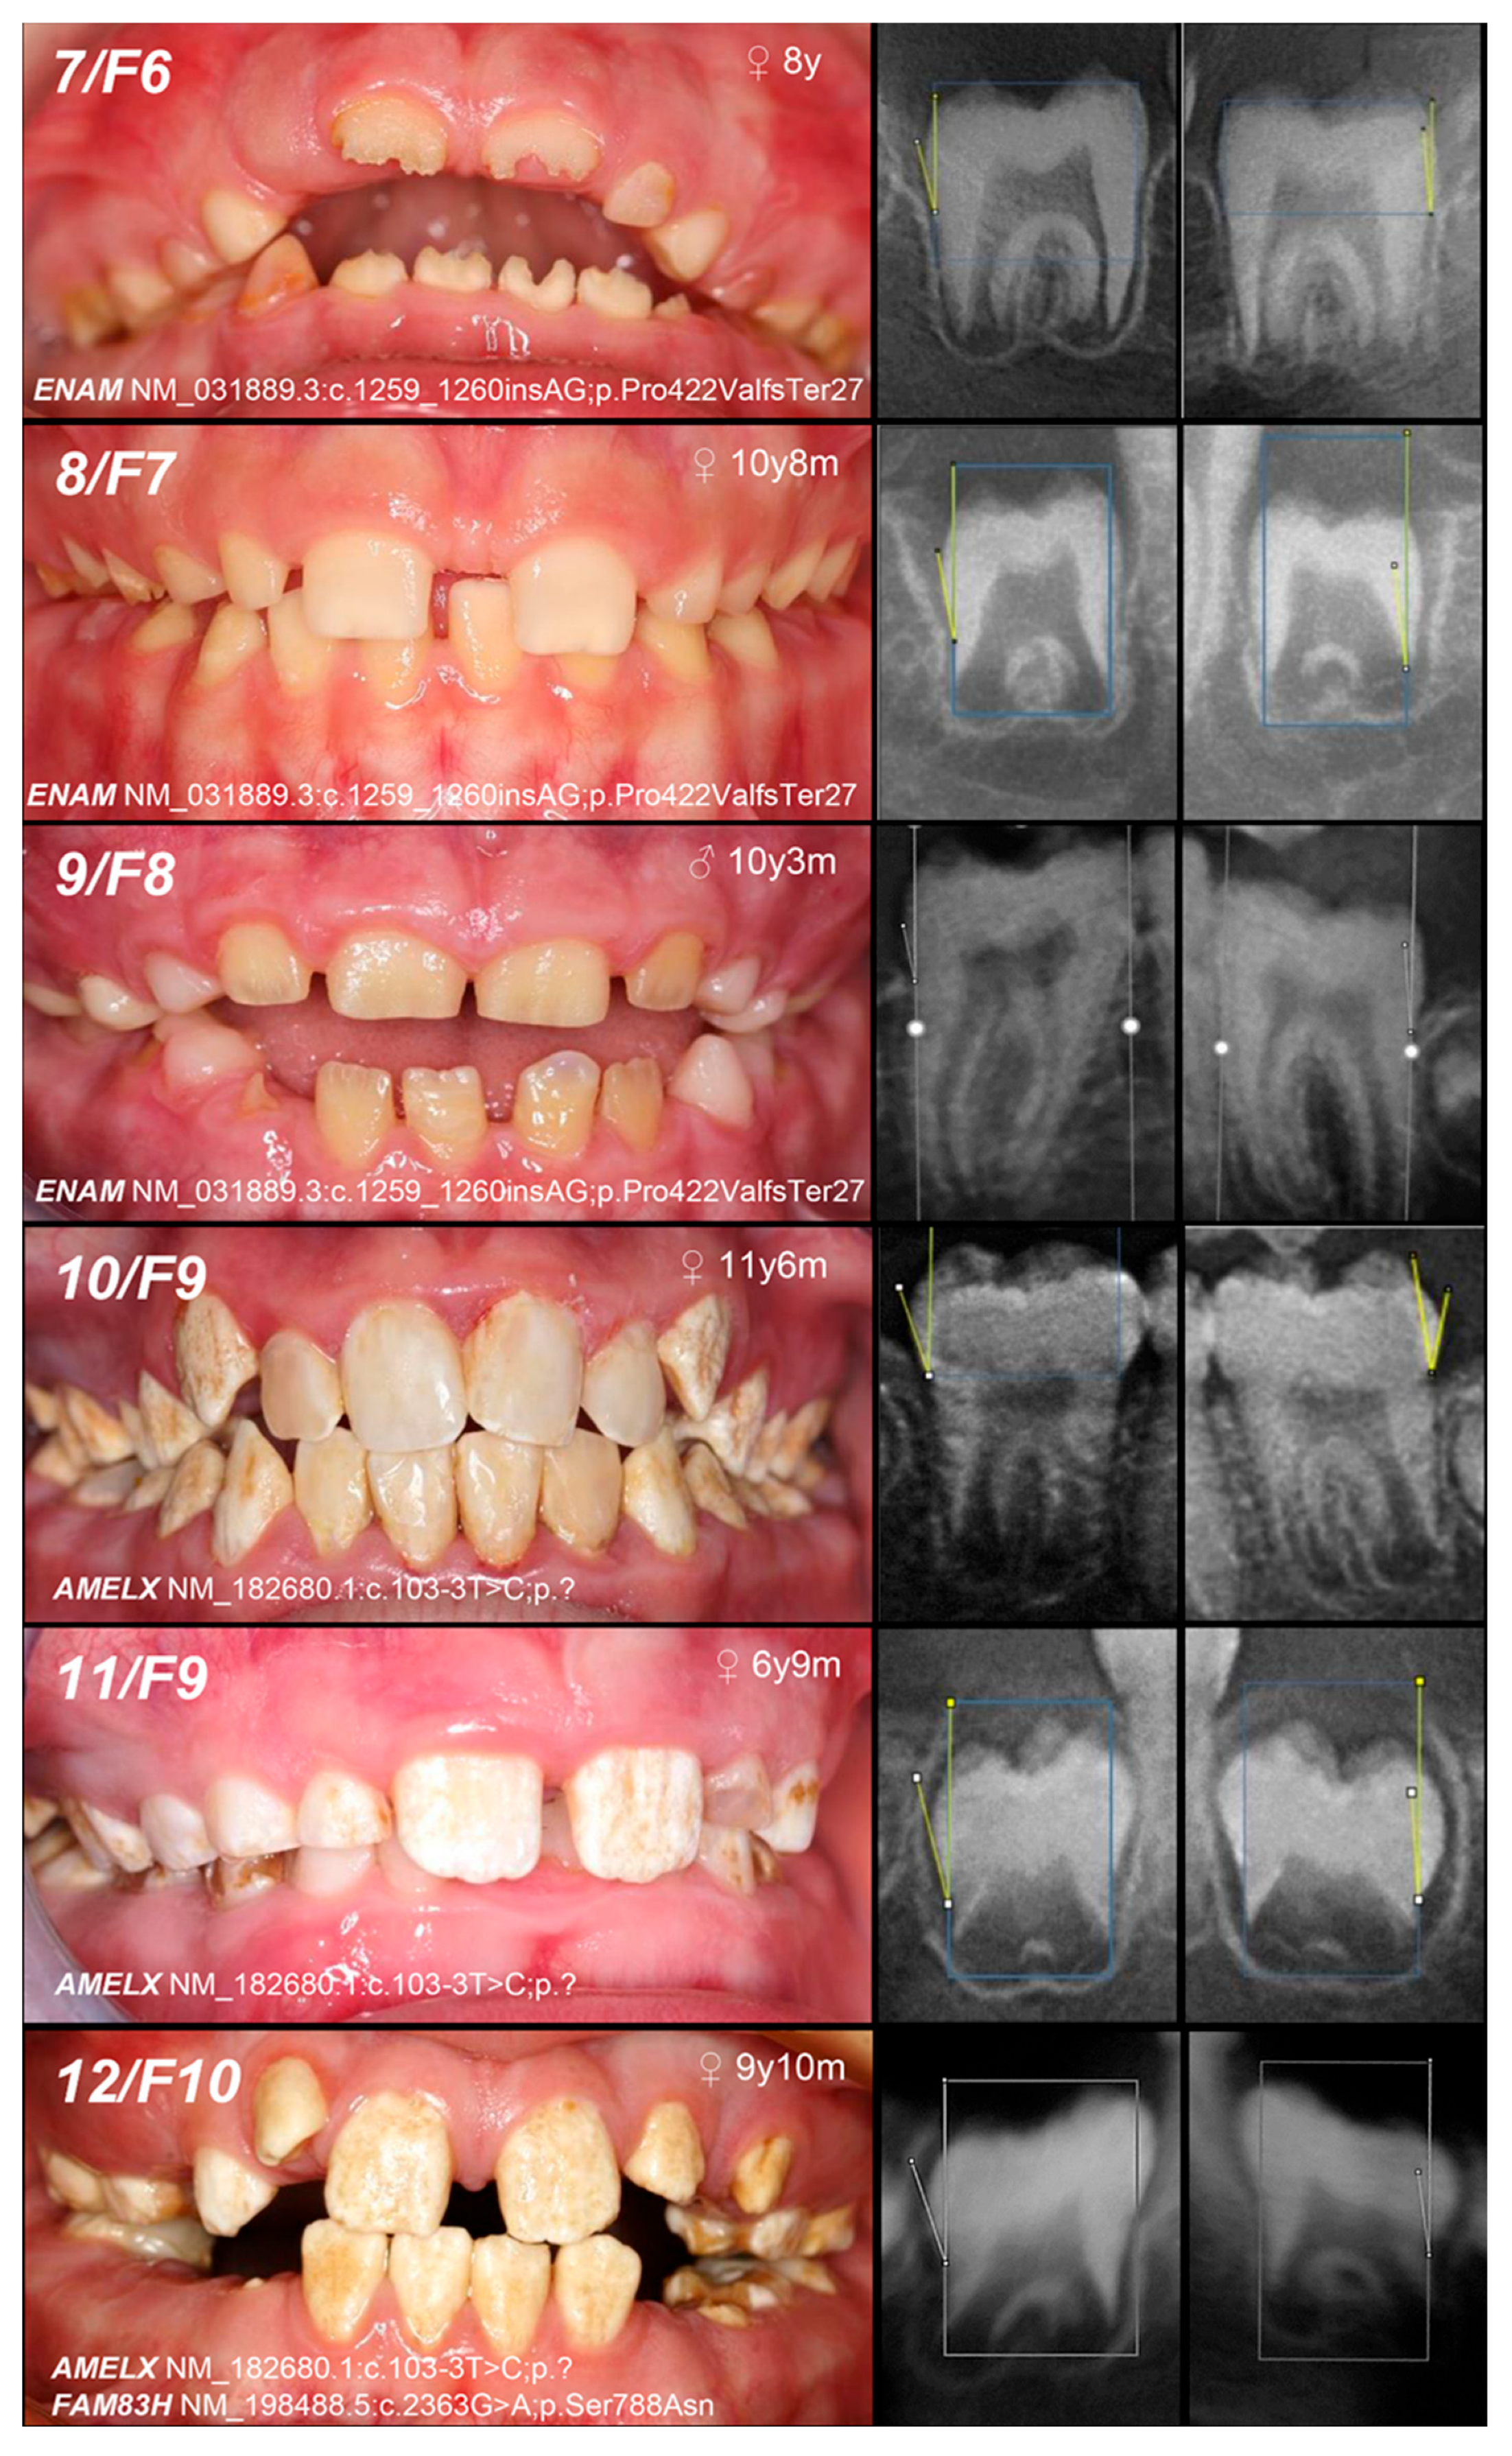

| 5, 6, F5 | Hypoplastic (generalized—recessive trait; localized, pitting, grooving—dominant trait) | IC, AR/AD, ENAM | −/− | [25] | MoFa (UC) | |||

| 7, F6 | MoFaS (UC) | |||||||

| 8, F7 | MoFa (UC) | |||||||

| 9, F8 | MoFa (UC) | |||||||

| 10, 11, F9 | Hypomineralized (heterogeneity) | IE, XLD, AMELX | c.103-3T>C | +/− | p.? | [26] | Mo(U) Fa (AC) | likely pathogenic (PP1:strong, PM2:moderate)* |

| 12, F10 | +/− | Mo (AC) Fa (NA) | ||||||

| and IIIA, AD, FAM83H | c.2363G>A | +/− | p.Ser788Asn | [26] | benign (BA1:stand-alone, BS2:strong, BP4:supporting, BP6:strong) | |||

| 13, F11 | Hypoplastic (heterogeneity) | IE, XLD, AMELX | c.485delT | 0/− | p.Phe162SerfsTer13 | novel | MoS (A) Fa (NA) | likely pathogenic (PVS1:very strong, PM2:moderate) |